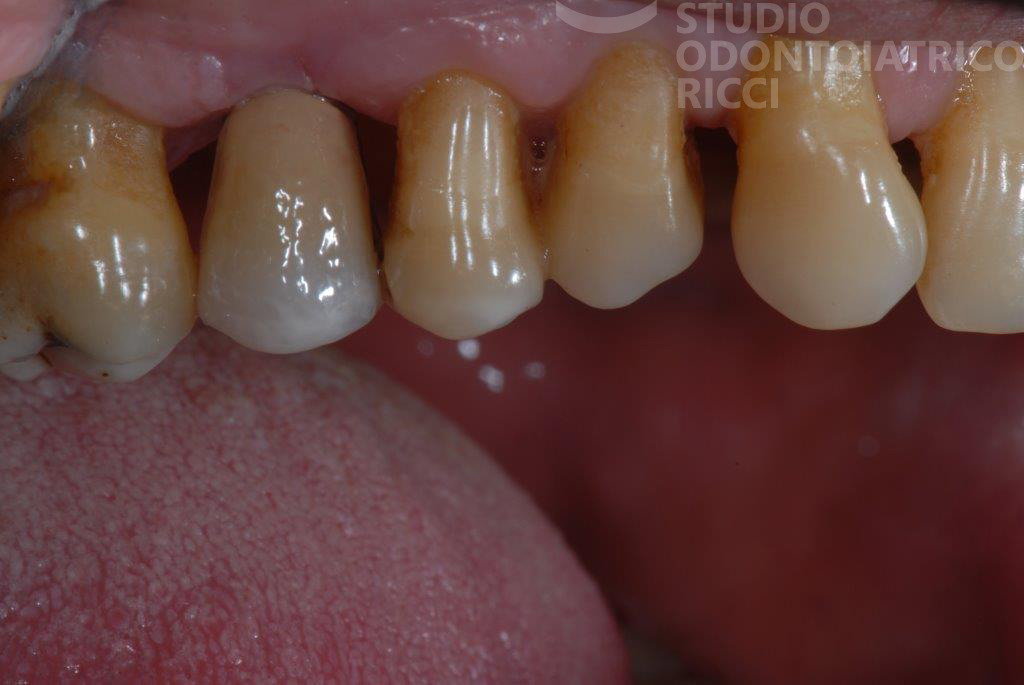

La maggior parte dei pazienti può sottoporsi a un trattamento implantare. È però fondamentale eseguire uno studio preliminare, con esami radiografici (es. TAC) per valutare:

quantità e qualità dell’osso

stato di salute generale

abitudini come fumo o bruxismo